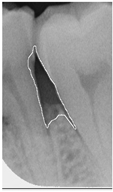

Table 14. Periodontal image validation with 5-fold CNN validation.

Ground Truth

Angle < 37

Bioengineering 12 00043 i001Bioengineering 12 00043 i002Bioengineering 12 00043 i003Bioengineering 12 00043 i004

Accuracy94.80% angle < 3797.53% angle < 3798.13% angle < 3797.65% angle < 37

Angle > 37

Bioengineering 12 00043 i005Bioengineering 12 00043 i006Bioengineering 12 00043 i007Bioengineering 12 00043 i008

Accuracy96.19% angle > 3796.30% angle > 3799.36% angle > 3798.37% angle > 37